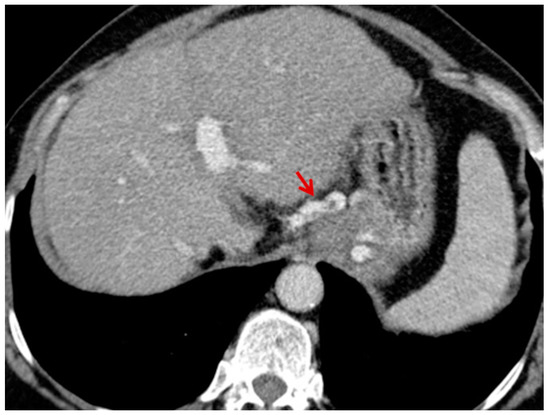

For this study, the images were retrospectively analyzed in consensus by two readers with experience in the field of abdominal imaging. The two readers assessed the following CT features: (1) The presence or absence of paraoesophageal varices and the size(mm) of the largest varix (Figure 1); (2) the presence or absence of paragastric varices and the size (mm) of the largest varix (Figure 2); (3) the largest diameter of the left gastric vein (Figure 3); (4) the presence or absence of splenorenal shunts and the size(mm) of the shunt (Figure 4); (5) the presence or absence of a repermeabilized round ligament and the size(mm) of it (Figure 5).

Figure 1. Axial contrast-enhanced CT shows enlarged paraoesophageal varices (red arrow).